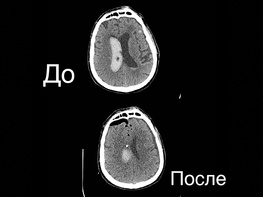

На базе нейрохирургического отделения Мариинской больницы при участии кафедры нейрохирургии ВМА им. С.М. Кирова в рамках обучающего мастер-класса по нейроэндоскопии проведена показательная операция по эндоскопическому удалению внутримозговой гематомы. Операция транслировалась в онлайн формате, за ее проведением наблюдали нейрохирурги со всей России.

Пациент 54-х лет поступил в экстренном порядке в реанимационное отделение. При обследовании было выявлено кровоизлияние в желудочки мозга. Операция по удалению гематомы из желудочков мозга позволит пациенту значительно быстрее выздороветь и вернуться к нормальной жизни.